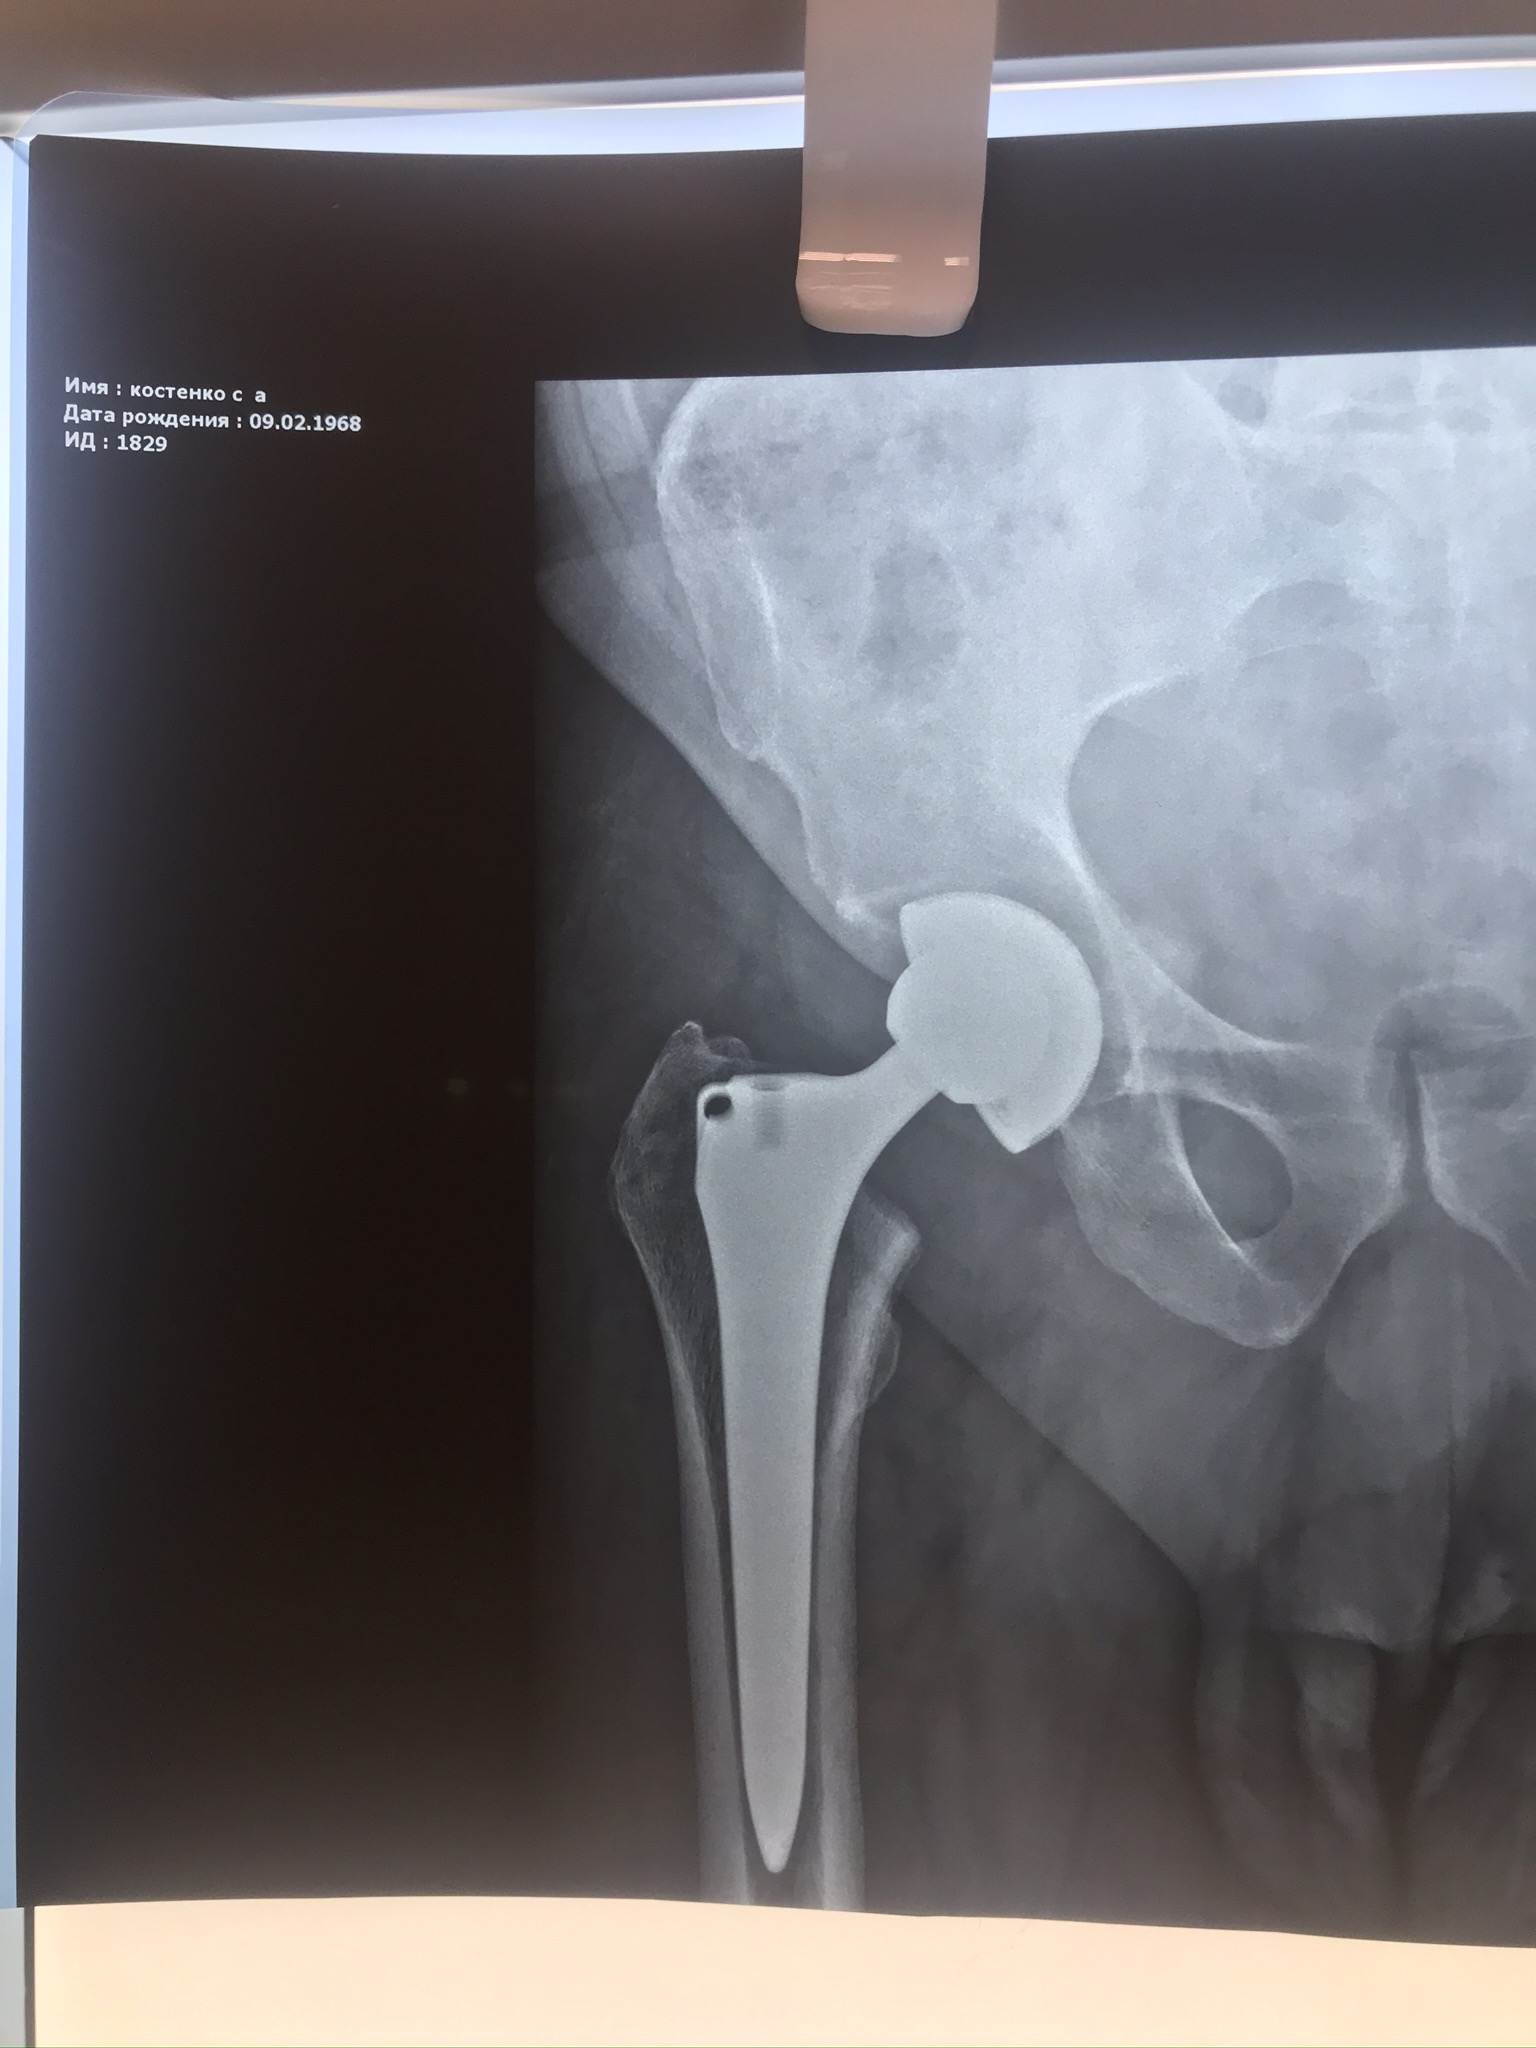

• ендопротезування великих суглобів (плечового, кульшового, колінного та голівки променевої кістки);